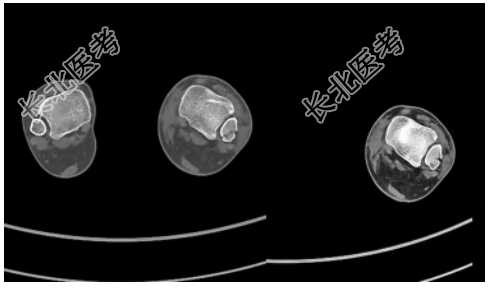

- [材料题] 患者,女,39岁,主诉“外伤致左踝部疼痛、活动受限1h”入院,就诊于日照市中医医院急诊外科。查体:左侧踝关节局部软组织肿胀压痛,后外侧压痛明显,踝关节活动受限,可触及足背动脉搏动,左侧下肢远端血运、感觉、活动未见明显异常。辅助检查:左侧胫腓骨(包括踝关节)X线片显示左侧腓骨远端骨折,骨折块在正位片被腓骨干遮挡(图1)。入院后完善踝关节CT检查,CT横断面显示左侧腓骨远端后侧骨折块,骨折块向胫骨侧移位,骨折线沿冠状面走形,左侧腓骨切迹为Ⅰ型,右侧腓骨切迹为C型(图2);CT矢状面显示左侧腓骨远端后侧骨折块,未累及腓骨干(图3)。CT三维重建显示左侧腓骨远端后侧类椭圆形骨折块,为明确有无下胫腓联合韧带断裂,完善MRI检查,MRI显示下胫腓前、后韧带均完整,下胫腓后韧带与骨折块相连(图4),牵拉骨折块向内侧移位,PDW序列显示下胫腓后韧带存在浅深两层且在部分层面存在融合。以上检查结果可明确诊断下胫腓后韧带腓骨端撕脱骨折。